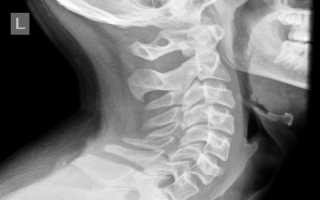

Проведение диагностики

Для постановки диагноза назначается рентгенография черепа и шейного отдела. Аномалия Киммерли чётко видна на рентгенограмме при обследовании краниовертебрального перехода. Если пациент жалуется на ушной шум, чтобы исключить лор-болезнь, требуется консультация отоларинголога. Проводится аудиометрия, при необходимости назначаются дополнительные методы исследования слуха.